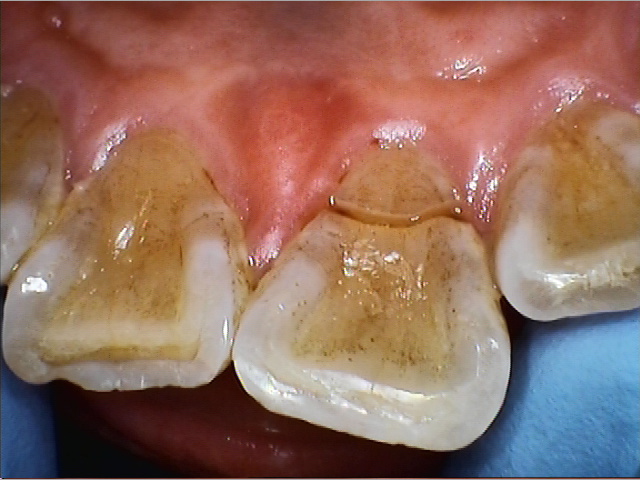

こちらの患者様は、「右上の前歯が折れてしまった」とのことで来院されました。

硬いものを噛んだ際にご自身の歯が破折しており、裏側には大きな割れ目が確認できました。

歯はグラグラと動揺し、残念ながらこのままでは安定して噛むことができない状態です。